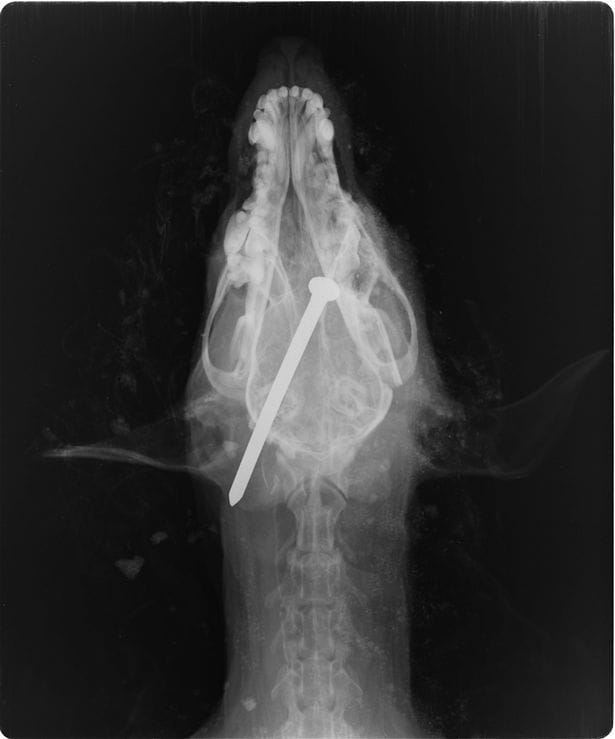

Michael Heathcock, âgé de 59 ans, affirme que son chien, Scamp, était aveugle et sourd. Il ajoute que l'animal peinait aussi à utiliser ses pattes arrière et qu'il était devenu incontinent. Face au coût élevé de l'euthanasie, Michael Heathcock, accompagné de Richard Finch, 60 ans, a décidé d'abréger lui-même les souffrances supposées de Scamp.Les deux hommes se sont emparés d'un marteau et de clous, puis ont emmené l'animal en pleine forêt, où Michael Heathcock lui a enfoncé un clou dans le crâne. Il a fallu six coups de marteau pour que la tige en métal transperce la tête de Scamp. Richard Finch, qui faisait le guet, a encouragé son ami à commettre ce crime atroce.

Scamp ne bougeait plus lorsque les deux hommes l'ont jeté dans un trou, persuadés que l'animal était mort.Le chien a cependant été secouru quelque temps plus tard par un couple en balade dans les bois. Encore en vie, Scamp implorait et gémissait sous le tas de terre recouvrant le trou où il avait été enterré.